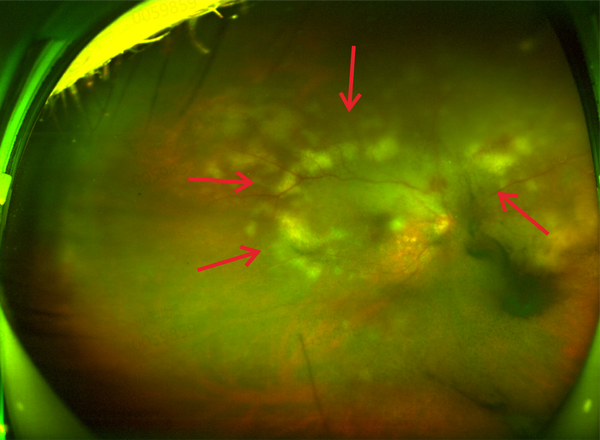

而且眼底照相也能看到视网膜水肿并乳白色混浊病灶,其内夹杂片状出血。

▲赵女士超广角眼底照相